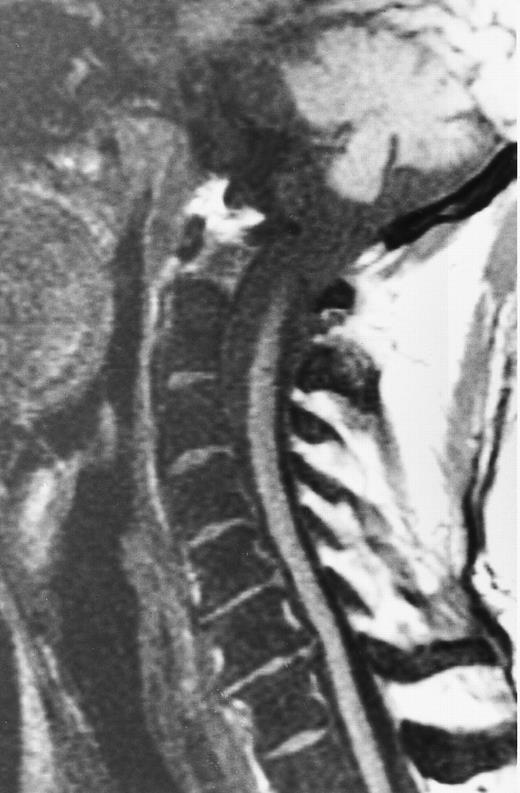

Diffuse MR pattern of abnormal marrow in a 29-year-old man with AML: T1-weighted sagittal (500/10, TR/TE) (A), T2-weighted, fat-suppressed fast spin echo sagittal (5000/96, TR/TE, ET 16) (B), and enhanced T1-weighted sagittal (500/10, TR/TE) (C) MR images of the thoracic spine. The abnormal vertebral bodies in (A) are dark and isointense to the intervertebral discs and in (B) they become bright. In (C), the abnormal marrow enhances and the vertebrae become brighter than the discs. Note extraosseous mass (arrowheads) in the posterior epidural space with preservation of the bony cortex.